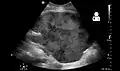

Imaging

Post operatively, kidneys are periodically assessed by ultrasound to assess for the imaging and physiologic changes that accompany transplant rejection. Imaging also allows evaluation of supportive structures such as the anastomosed transplant artery, vein, and ureter, to ensure they are stable in appearance.

Postoperative bleeding following kidney transplant as seen on ultrasound[55]